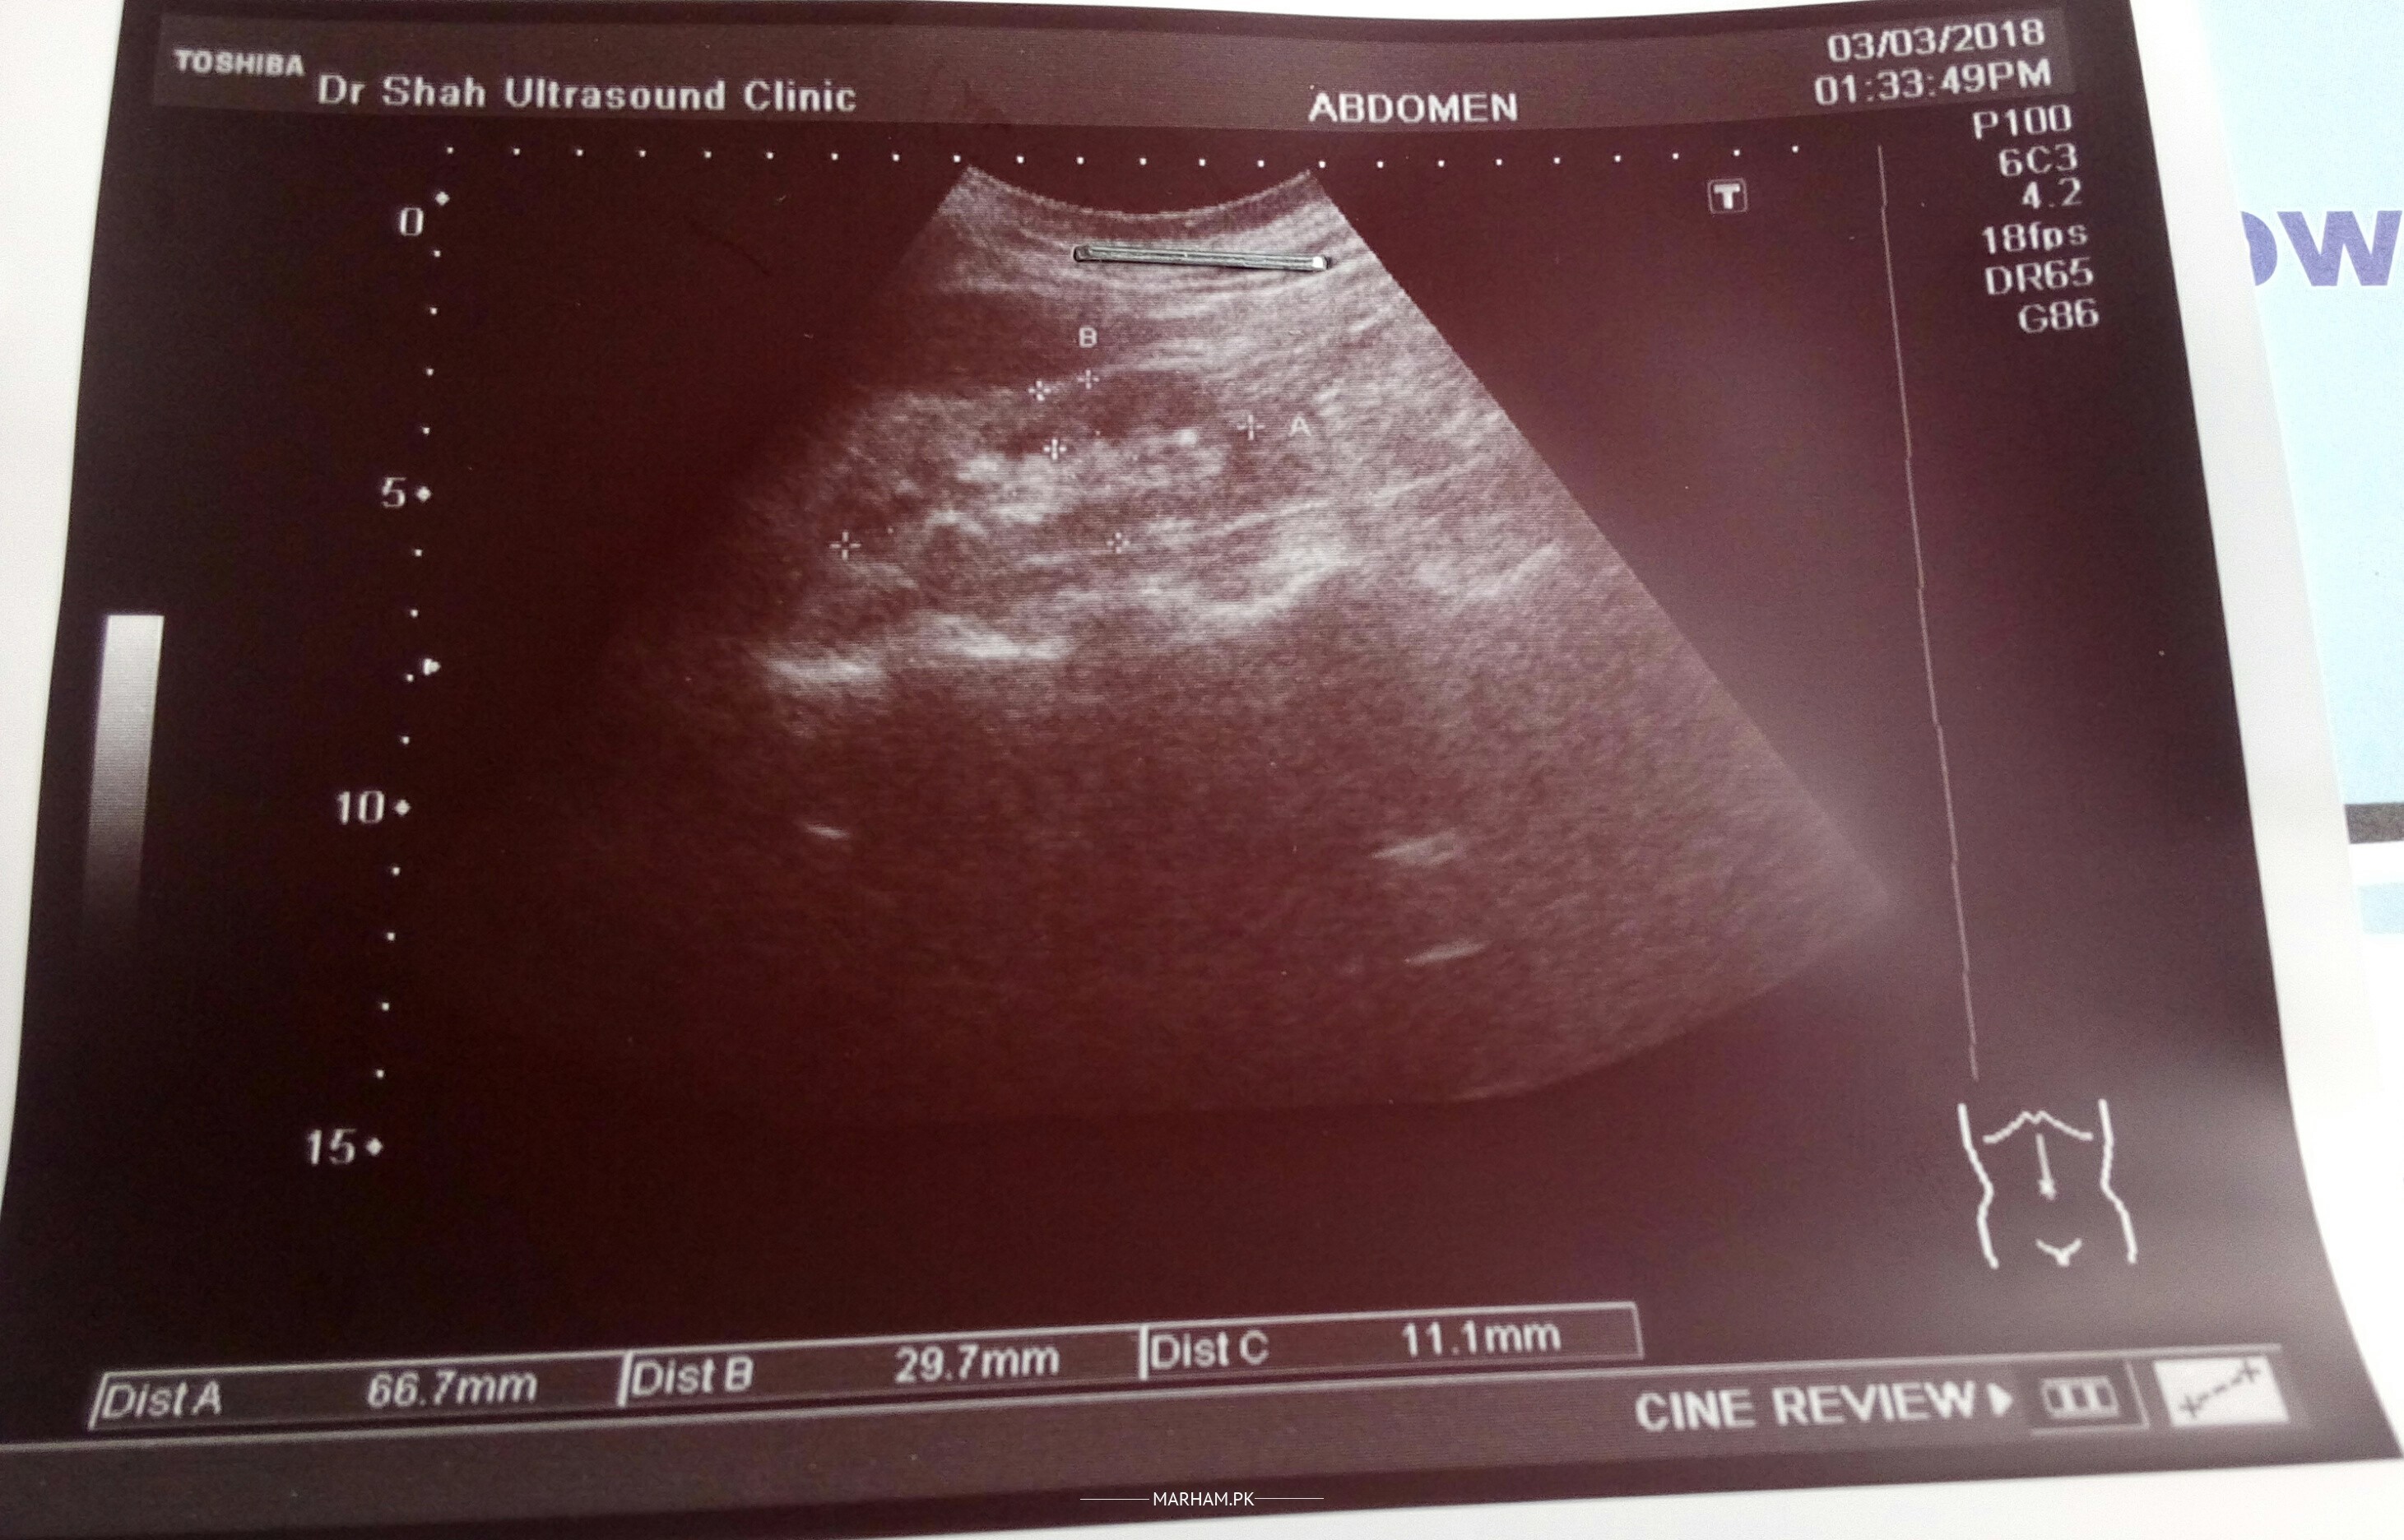

Doctors especially nephrologist . please see this ultrasound are the kidneys?about size and shape?(Rt.78x26.2x9.5mm).(left.66.7x29.7x11.1mm) size is in some one tell me?

Kidneys are relativly smaller and echogenic